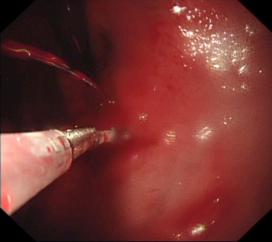

1. 內(nèi)鏡下止血術(shù):采用內(nèi)鏡下微創(chuàng)治療方法,有效止血,成功率達(dá)95%以上;凡來我院的消化道出血病人晝夜24小時(shí)內(nèi)均可得到急診胃腸鏡的及時(shí)診治,使消化道出血病人的死亡率、并發(fā)癥及診治費(fèi)用均大幅降低;

胃底潰瘍并出血止血術(shù)